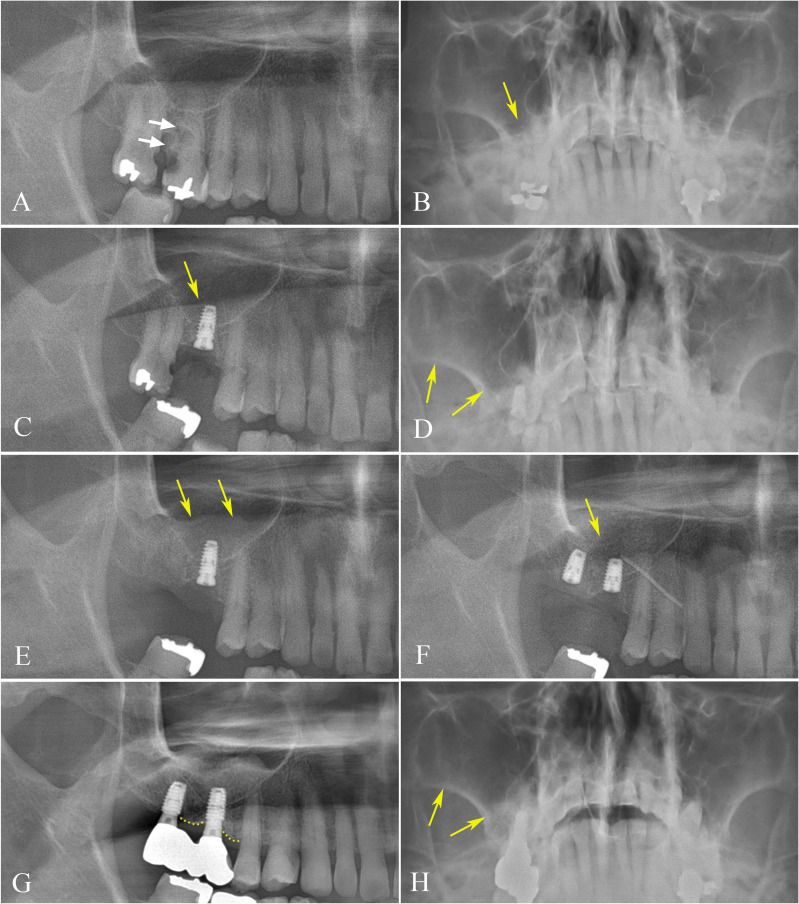

Methods: Between 2009 and 2018, a single surgeon at Seoul National University Dental Hospital in Seoul, Korea, immediately inserted 49 dental implants with tapered bone-level design after extraction, in a total of 34 patients. The clinical outcomes were collected and evaluated, focusing on location of implant placement and marginal bone loss (MBL), with consideration of other parameters such as implant diameter and length.

Results: Of 49 immediately installed Luna® (Shinhung Co., Seoul, Korea) dental implants, 23 were placed in the mandible, and 26 were set in the maxilla. The mean age of patients at the time of installation was 65.91 years, ranging from 40 to 86 years. The average follow-up period was 7.43 years, with a range of 5 to 14 years. After a 5-year retrospective evaluation of tapered, sand-blasted, and acid-etched internal submerged dental implants for immediate implant placement, the cumulative survival rate was 93.88%, with 100% survival rate in the mandible and premolar region of both the maxilla and mandible.